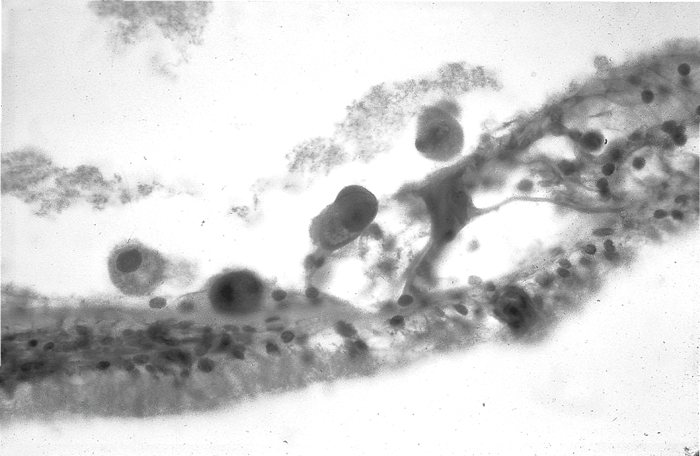

Congenital CMV: investigations and management in the audiology setting

Congenital cytomegalovirus (cCMV) is the only cause of congenital sensorineural hearing loss (SNHL) for which there is a medical treatment available to prevent further hearing loss. Dr Simone Walter discusses cCMV infection, cCMV-related hearing loss, and how to facilitate their...